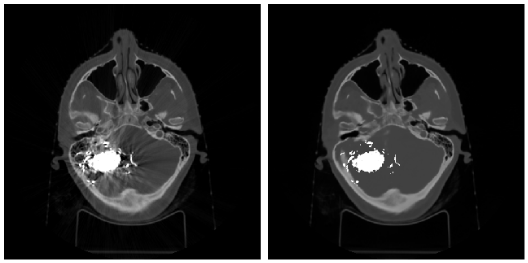

Embolic agents injected during the first stage of this treatment can be divided into solids (for example, metal coils) and liquids. Metal components of the embolic agents, as well as coils’ metal body, cause severe artifacts on CT scans, producing both bright regions of high absorption and dark regions of low absorption. Several studies have proposed that the presence of these high-density objects induces beam hardening artifacts on CT scans and might distort the dose calculation accuracy of the radiosurgery planning [6]. Figure 1 shows CT scans of two patient with AVMs after embolization (see more technical details on types of embolization in Section III-A).

Refer to caption

Figure 1: Liquid (left) and solid (right) embolization of the AVMs with notable artifacts on the CT images due to the metal components of the embolic materials.